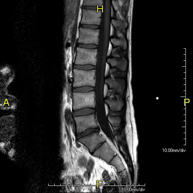

- Lumbar spine MRI

This non-invasive diagnostic procedure uses an electromagnetic field and radio waves (from a transmitter and receiver) to acquire high-definition anatomical images of the lumbar and sacral regions. It is a radiation-free procedure. Indicated for: trauma, sciatica, herniated discs, tumours, infections.

- Sacrum-coccyx MRI

This non-invasive diagnostic procedure uses an electromagnetic field and radio waves (from a transmitter and receiver) to acquire high-definition anatomical images of the sacrum and coccyx. It is a radiation-free procedure. Indicated for: sacrococcygeal pain, trauma.